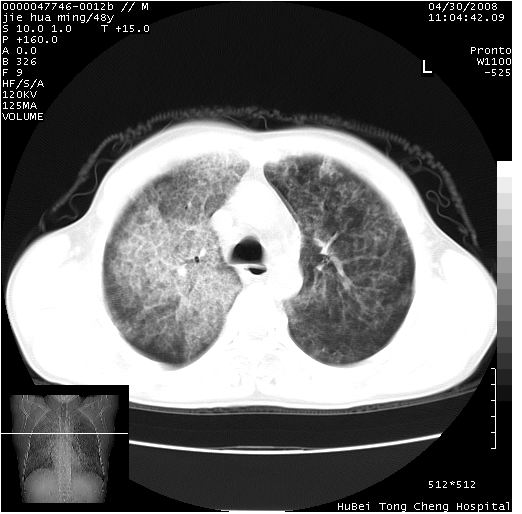

以下是引用dr.yang在2008-5-1 6:25:00的发言:[br]两肺广泛毛玻璃样的片状影,密度不均,边缘欠清,呈碎石路样改变,[br]考虑,1双肺间质性肺炎,2肺泡蛋白沉积症3支气管肺泡癌[br]

以下是引用hhcckk在2008-5-1 8:06:00的发言:[br]支持肺泡蛋白沉积症[br]依据:[br]1、病灶边缘清楚----地图征[br]2、病灶内部小叶间隔或小叶内间隔增厚所形成的网格状影----碎石路样表现[br]3、抗炎治疗无效(炎症抗炎治疗有效)[br]4、纵隔内未见肿大淋巴结(肺泡细胞癌时常有)[br][br]附肺泡蛋白沉积症资料[br][br]肺泡蛋白沉积症(pulmonary alveolar proteinosis)是一种原因不明的以肺泡腔内大量含脂糖蛋白样物质沉积为特征的疾病。[br]病理改变:(1)肺泡和细支气管腔内充满大量含脂糖蛋白样的粘稠物质,该物质为颗粒状或絮状的糖原pas染色阳性的磷脂蛋白。(2)肺泡壁及其间隔无异常改变。胸膜和淋巴结不受累及。(3)晚期可出现弥漫性肺间质纤维化。[br]临床表现:(1)好发年龄30~50岁,男性多于女性,偶见于儿童;(2)主要症状为呼吸困难、咳嗽、低热、消瘦、低氧血症和杵状指等。1/3的患者无症状。(3)实验室检查:痰液或肺泡灌洗液中可找到pas染色阳性颗粒物质。[br]hrct表现:肺泡蛋白沉积症具有特征性改变,即“碎石路样”表现(crazy-paving appearance,cpa)。主要包括(1)斑片状磨玻璃影:指肺野密度朦胧增加,内可见肺血管纹理影,系肺泡腔内充满低密度的磷脂蛋白物质所致。(2)其内部小叶间隔或小叶内间隔增厚所形成的网格状影,为小叶间隔水肿、肺泡壁内淋巴细胞和巨噬细胞浸润以及小叶内淋巴管扩张的缘故。(3)病灶边缘清楚,呈地图样分布于肺野外围或肺门及中央区。[br]

以下是引用zsl6918在2008-5-1 7:35:00的发言:[br]双肺磨玻璃样病变,可见铺碎路石征,病变区与正常区交错。边界清晰。符合肺泡蛋白质沉着征,高分辨扫描会更清楚漂亮。建议临床肺泡灌洗。

以下是引用yangyudong333在2008-5-1 5:36:00的发言:[br][br] 两肺广泛毛玻璃样的片状影,密度不均,边缘欠清,呈碎石路样改变,[br]考虑,1双肺间质性肺炎,2肺泡蛋白沉积症[br]